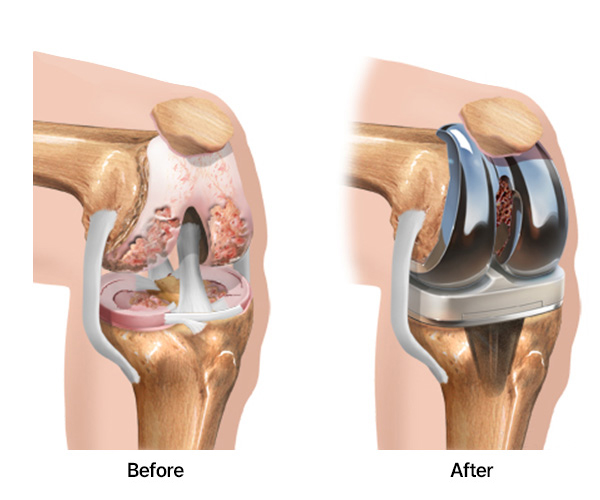

¹«¸­ ¼ö¼úÀº ¹Ý¿ù»ó¿¬°ñÆÄ¿­À̳ª ¿¬°ñÀÇ °æ¹ÌÇÑ ¼Õ»óÀÎ °æ¿ì °üÀý°æ ¼ö¼ú, °ñ°üÀý¿°ÀÌ ½ÉÇÑ °æ¿ì Àΰø°üÀý ġȯ¼úÀ» ¹Þ½À´Ï´Ù.